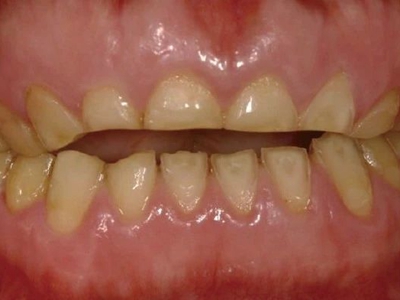

牙齿

黄斑

酸蚀症牙齿有不规则黄斑图

酸蚀症患者的牙齿会有黄斑形成,形状不规则,境界不十分清楚,呈茶渍样,尚未出现牙齿骨质缺损,需积极控制病因,避免进食酸性食物。